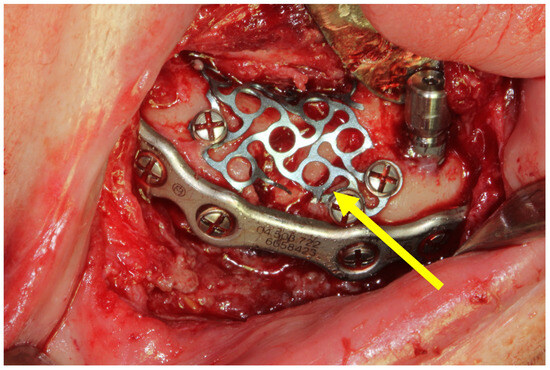

3.2. Case 2